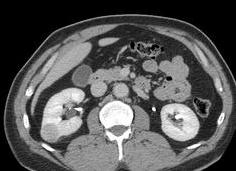

- КТ и МРТ.